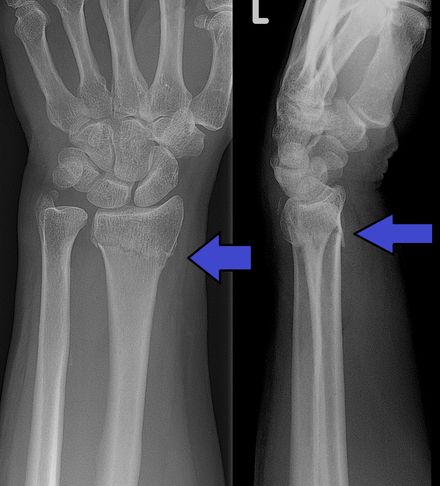

tisdag 29 maj 2018 AI som kan upptäcka frakturer godkänd i USA Det kommer bli mycket AI inom sjukvården i framtiden Det amerikanska läkemedelsverket FDA har godkänt ett AI-baserat system för att upptäcka frakturer i patienters handleder. Systemet kallas för OsteoDetect och AI:n är tränad för att upptäcka så kallade distala radiusfrakturer, det som vi vanligtvis kallas för handledsfrakturer eller handledsbrott. Tanken med systemet är inte att det ska ersätta läkare utan OsteoDetect ska istället användas som ett komplement när läkaren ställer sin diagnos. Tidigare i år har FDA bland annat godkänt AI-baserade system för att upptäcka ögonsjukdomar såväl som att upptäcka stroke-fall. Tumnagel